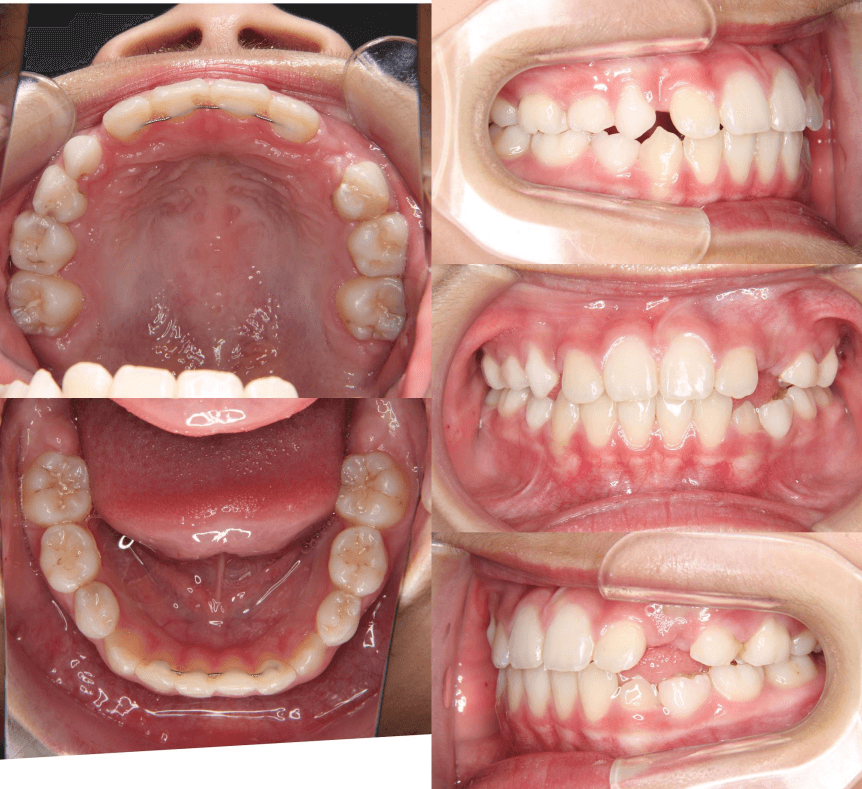

早期矯正治療 開咬症例

主訴 | 前歯がしっかり噛み合わず、食事時に違和感を覚えて来院された患者様です。 |

---|---|

診断結果 | 6歳6か月の女児。 上下の前歯が接触せず隙間があり、開咬と診断されました。 |

治療内容 |

|

治療後の経過 | 1年11か月間の動的治療により、前歯の噛み合わせが改善されました。現在は3〜4か月ごとに定期検診を行い、上下顎の骨の成長や永久歯の萌出状況を確認しながら、本格矯正治療のタイミングを検討しています。 |

治療期間 | 動的治療期間:1年11か月 治療回数:18回 |

治療費用 | 400,000円(税別) |